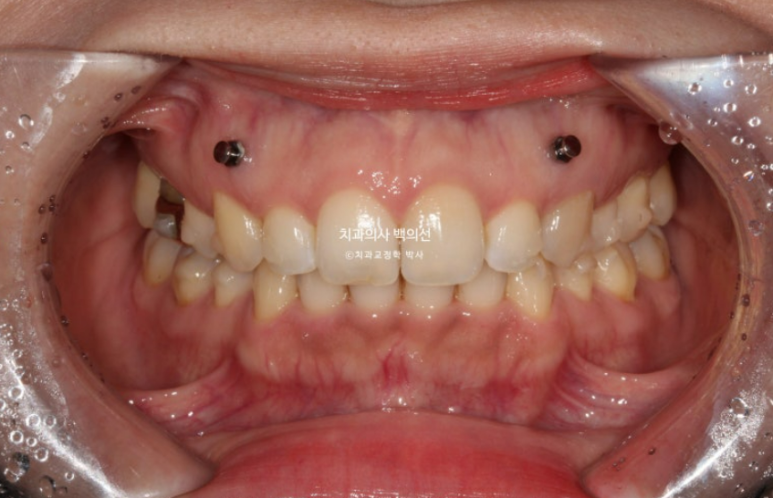

24년 10월부터 25년 4월까지 6개월간 14개의 추가장치를 다 낀 후 모습입니다.

과개교합은 더 개선이 되었고

발치공간은 타이트하게 마무리가 되어 철사유지장치까지 부착했습니다.

앞니가 깊게 물리는 과개교합이 개선되어 비로소 철사유지장치를 붙일 수 있었습니다.